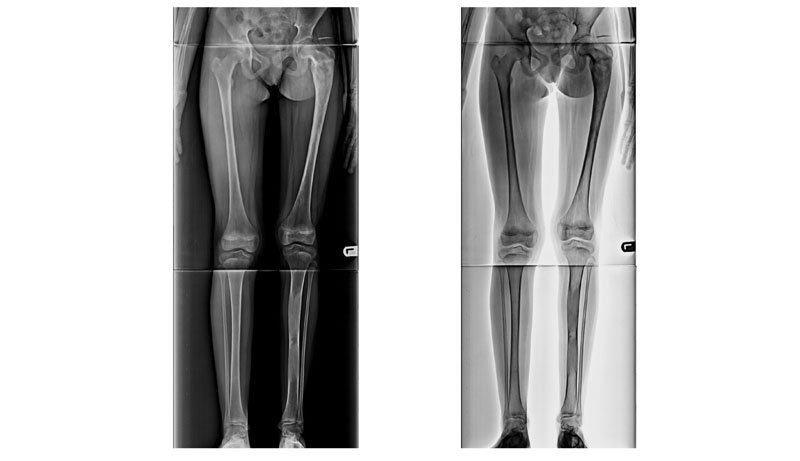

1 : For planning of any realignment operation of lower limb, mainly for genu valgus & varus deformity due to osteoarthritis / post # healing. 2 : To measure limb length discrepancy - congenital/acquired. 3 : For evaluation of kyphoscoliosis spinal dysraphism or identification of curve apex, end vertebra, neutral vertebra, stable vertebra, major V/S minor curves, structural V/S non-structural curves.